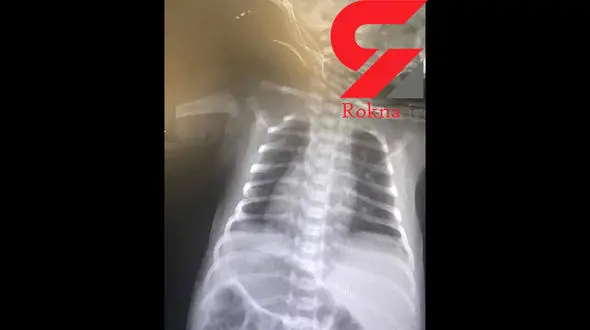

رکنا: نوزادی که قلب و معده او در سمت راست قرار دارد در گراش متولد شده است.